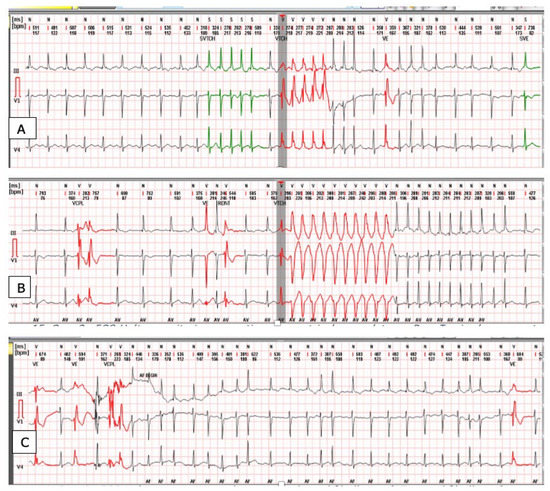

3.1. Case 1

3.2. Case 2

3.3. Case 3